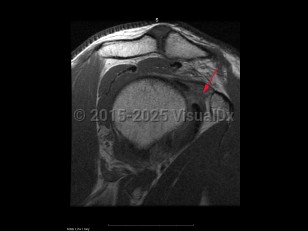

Classic history and presentation: Adhesive capsulitis typically follows a course of 3 phases. First (2-9 months), there is an insidious onset of pain that eventually becomes severe and disabling. The pain tends to be worse at night and stiffness gradually onsets. Second (4-12 months) is the contracture phase, which is characterized by stiffness and progressive loss of motion that interferes with activities of daily living. Pain typically improves in this phase. Third (5-24 months) is the recovery or "thawing" phase in which the symptoms gradually alleviate and there is an improvement in range of motion (ROM).